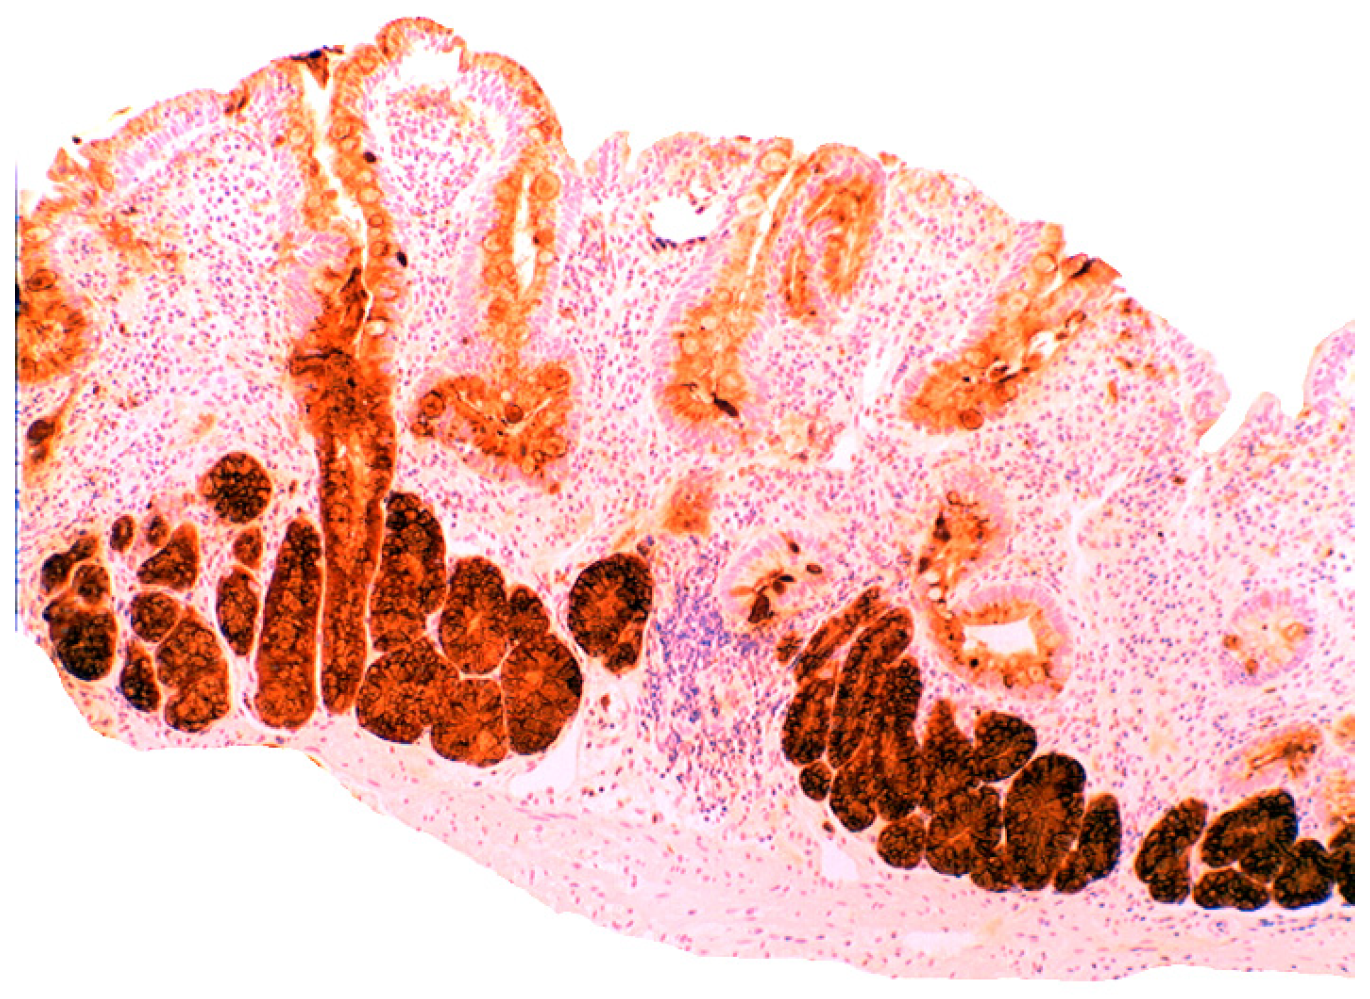

3.5. Lysozyme Is Up-Regulated in Chronic Gastritis, Intestinal Metaplasia, Autoimmune Gastritis and Fundic-Gland Polyps

In chronic gastritis lysozyme is up-regulated in the neck region of the oxyntic mucosa, in antral pyloric glands (Figure 5) and in the surface-foveolar epithelium of the oxyntic mucosa [8]. In cases with in intestinal metaplasia, lysozyme is up-regulated in goblet cells (Figure 6), and in Paneth cells. In cases with autoimmune gastritis, lysozyme is up-regulated in pseudo-pyloric glands (Figure 7).

Chronic gastritis (antrum) showing lysozyme expression in surface epithelium, and in antro-pyloric glands (lysozyme immunostain, ×10).

Figure 6.

Chronic gastritis with intestinal metaplasia. Left panel: Oxyntic (corpus) mucosa showing lysozyme expression in goblet cells and in mucus neck cells. Note absence of lysoyme expression in parietal cells in the lower part of the picture (below arrows); Right panel: Antro-pyloric mucosa showing lysozyme expression in goblet cells and in Paneth cells at the bottom of the crypts (arrows, lysozyme immunostain, ×10).